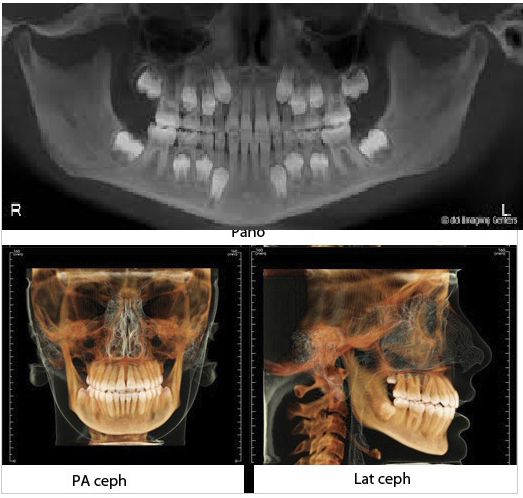

2D IMAGING

TRUE Pano:

A Panoramic like no other. Doing away with all the limitations of the conventional pan, the INsightPano delivers a crystal clear image, when getting the diagnosis right, is of paramount importance

Ceph:

Stunning Lat. as well as PA Cephs with well defined ,easily recognisable landmarks, coupled with an unmatched soft tissue profile

Orthodontics

• 3D evaluation of craniofacial structures (no more gray-scale Cephalograms)

• Exact positioning of impacted & unerupted teeth

• Cephalogram images can be superimposed on various stable structures and changes quantified in all planes of Space

• Depiction of skeletal asymmetries with volume rendering

• Accurate placement of mini implants - along with required analysis of bone quality & quantity